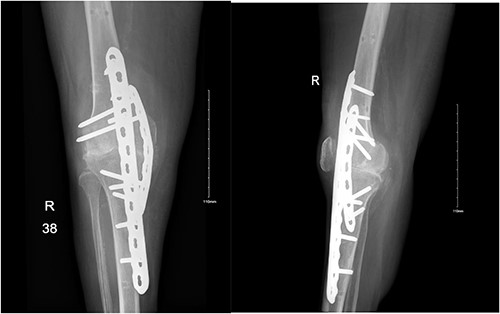

Three days following her external fixator removal, she presented to the ED with a history of severe knee pain and a loud clicking sound after trying to ambulate. Her X-ray showed a recurrent knee dislocation. The patient was then admitted and booked for a prophylactic I&D, which showed no signs of septic arthritis and later underwent an arthrodesis of the right knee (Fig. 2). The decision of arthrodesis was made after clearing out infection, and to eliminate further dislocation concerns.

Anteroposterior and lateral views of the knee following arthrodesis.